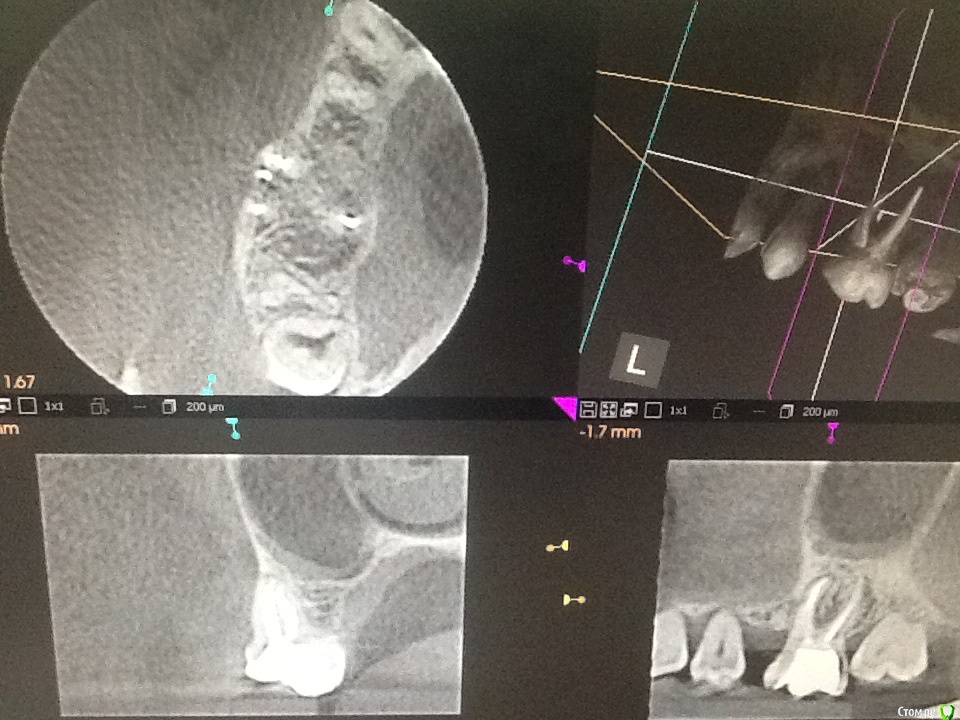

Л Ю С Я Опубликовано 25 ноября, 2015 Поделиться Опубликовано 25 ноября, 2015 (изменено) После удачного эндо ( если причина в этом) в пазухе все будет хорошо. Полечили пульпит , через 6 месяцев прислали от лориков с подозрением на одонтогенныйЧерез 6 месяцев после перелечивания Изменено 25 ноября, 2015 пользователем Л Ю С Я 1 Ссылка на комментарий

Сева северный Опубликовано 25 ноября, 2015 Поделиться Опубликовано 25 ноября, 2015 После удачного эндо ( если причина в этом) в пазухе все будет хорошо. Полечили пульпит , через 6 месяцев прислали от лориков с подозрением на одонтогенныйimage.jpegimage.jpegЧерез 6 месяцев после перелечиванияimage.jpegimage.jpegДа показательно..... У меня с одонтогенными ЛОР проблемми чаще вот так.. Ссылка на комментарий

Л Ю С Я Опубликовано 25 ноября, 2015 Поделиться Опубликовано 25 ноября, 2015 немножечко не так...Рекол это святое...я рассматриваю различные варианты лечения, со сроком службы минимум 10 лет.. Если ты понимаешь, что этот зуб будет стоять лет 5-ть. постоянно мучая пациента, а потом все равно удалится.. да еще со значительным ухудшением прогноза. лучше поступить радикально.Кстати у этой пациентки через 2 недели, после удаления, все прошло. ЛОРа она не посещает ...Специально спрашивал. Так что, все как всегда, индивидуально..(((Этот зуб будет мучить пациента если эндо проведено неудачно, не получилось, не удалось и т д. Если с эндо все в порядке, на реколле положительная динамика, я вот уверена, что там срок службы больше 10 лет, при условии изготовления хорошей коронки . Если не сложно, ответьте , пожалуйста , через сколько после удаления сделан снимок, здесь явно не через 2 недели Ссылка на комментарий

Л Ю С Я Опубликовано 25 ноября, 2015 Поделиться Опубликовано 25 ноября, 2015 Повторное Кт было сделано через 6 месяцев.. Для сохранения обьемов кости, удаление было сделано с костной пластикой. Сейчас, предстоит имплантация. терапевт...хирург и ортопед .на один и тот же зуб смотрит по разному...Это данность.Может быть и так. Но должны быть положительные результаты. Когда я показываю свои результаты эндо после 2,4 лет наблюдения хирургам, которые были категорически против лечения, доводы такие: нуачерез 10 лет? А Вы можете гарантировать , что не будет переимплантита через 10 лет? 1 Ссылка на комментарий